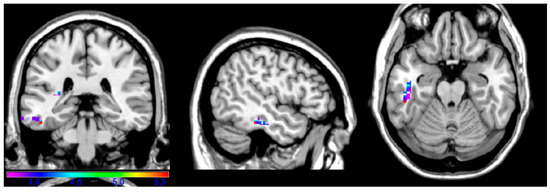

Ideomotor apraxia is a cognitive disorder most often resulting from acquired brain lesions (i.e., strokes or tumors). Neuroimaging and lesion studies have implicated several brain regions in praxis and apraxia, but most studies have described (sub)acute patients. This study aimed to extend previous [...] Read more.

Ideomotor apraxia is a cognitive disorder most often resulting from acquired brain lesions (i.e., strokes or tumors). Neuroimaging and lesion studies have implicated several brain regions in praxis and apraxia, but most studies have described (sub)acute patients. This study aimed to extend previous research by analyzing data from 115 left hemisphere chronic stroke patients using the praxis subtest of the Western Aphasia Battery, which is divided into four action types: facial, upper limb, complex, and instrumental. Lesion–symptom mapping was used to identify brain regions most critically associated with difficulties in each of the four subtests. Complex and instrumental action deficits were associated with left precentral, postcentral, and superior parietal gyri (Brodmann areas 2, 3, 4, 5, and 6), while the facial and upper limb action deficits maps were restricted to left inferior, middle, and medial temporal gyri (Brodmann areas 20, 21, 22, and 48). We discuss ideas about neuroplasticity and cortical reorganization in chronic stroke and how different methodologies can reveal different aspects of lesion and recovery networks in apraxia. Full article

Show Figures

Figure 1